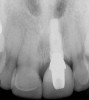

Figure 5h  Postoperative radiographs.

Figure 5h

Figure 5g  Postoperative radiographs.

Figure 5i